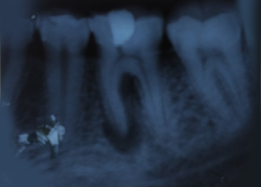

Pre-OP IOPAR

Hemisectomy